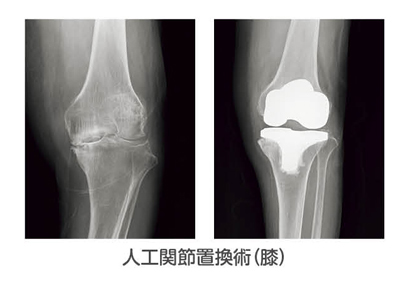

人工関節置換術

膝や股、肘、肩関節などに行われ、素材や手技の改良とともに、耐用年数も大きく伸びており、医療技術の進歩により、高齢の患者さまでも積極的にこの手術が行われるようになりました。